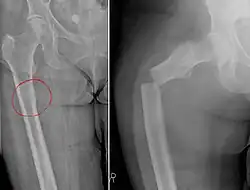

| Chalkstick fracture due to bone metastasis of breast cancer. The left image shows the metastasis, on the right a pathological fracture a few days later. | |

Chalkstick fractures are fractures, typically of long bones, in which the fracture is transverse to the long axis of the bone, like a broken stick of chalk.[1] A healthy long bone typically breaks like a hard woody stick as the collagen in the matrix adds remarkable flexibility to the mineral and the energy can run up and down the growth rings of bone. The bones of children will even follow a greenstick fracture pattern.